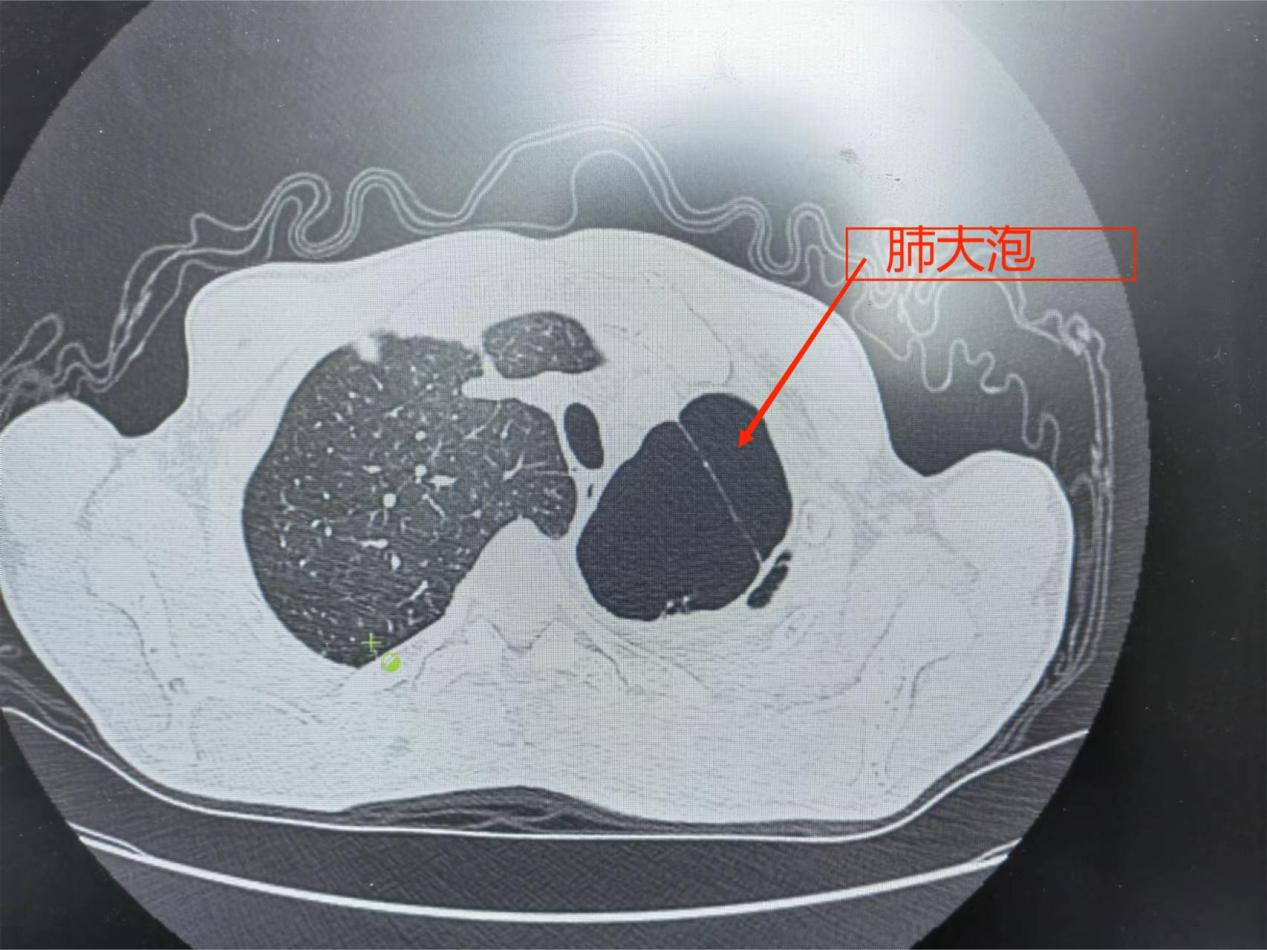

1月29日九江学院第二附属医院呼吸内科付云杰主任团队在胸外科张毅博士、麻醉科李成涛主任的协助下,成功为一例重度慢阻肺患者成功实施经无痛支气管镜双肺EBV活瓣肺减容术,一次性为患者处理了双侧肺大泡。术后患者即可起床活动,饮食照常,完全无痛,胸闷、气喘症状得到明显缓解,效果立杆见影。这是我院第二例支气管镜单项活瓣肺减容术,也是九江地区首例双肺支气管活瓣肺减容术。标志着我院支气管镜介入技术迈入新台阶,将造福更多九江乃至周边区域的患者!

据悉,经支气管镜单向活瓣肺减容术,是一种支气管镜下介入治疗的新技术,放置在支气管内的活瓣,允许分泌物和气体从活瓣远端肺组织排出,但阻止气体进入活瓣远端肺组织,从而使靶肺组织逐渐萎陷不张,达到减容的目的。该新技术具有疗效显著、创伤小、病人耐受好、术后康复快、并发症少和住院时间短等优势。经支气管镜单向活瓣肺减容术的成功开展,为广大不均质肺气肿表型、叶间裂完整的慢性阻塞性肺疾病患者带来了新的选择。